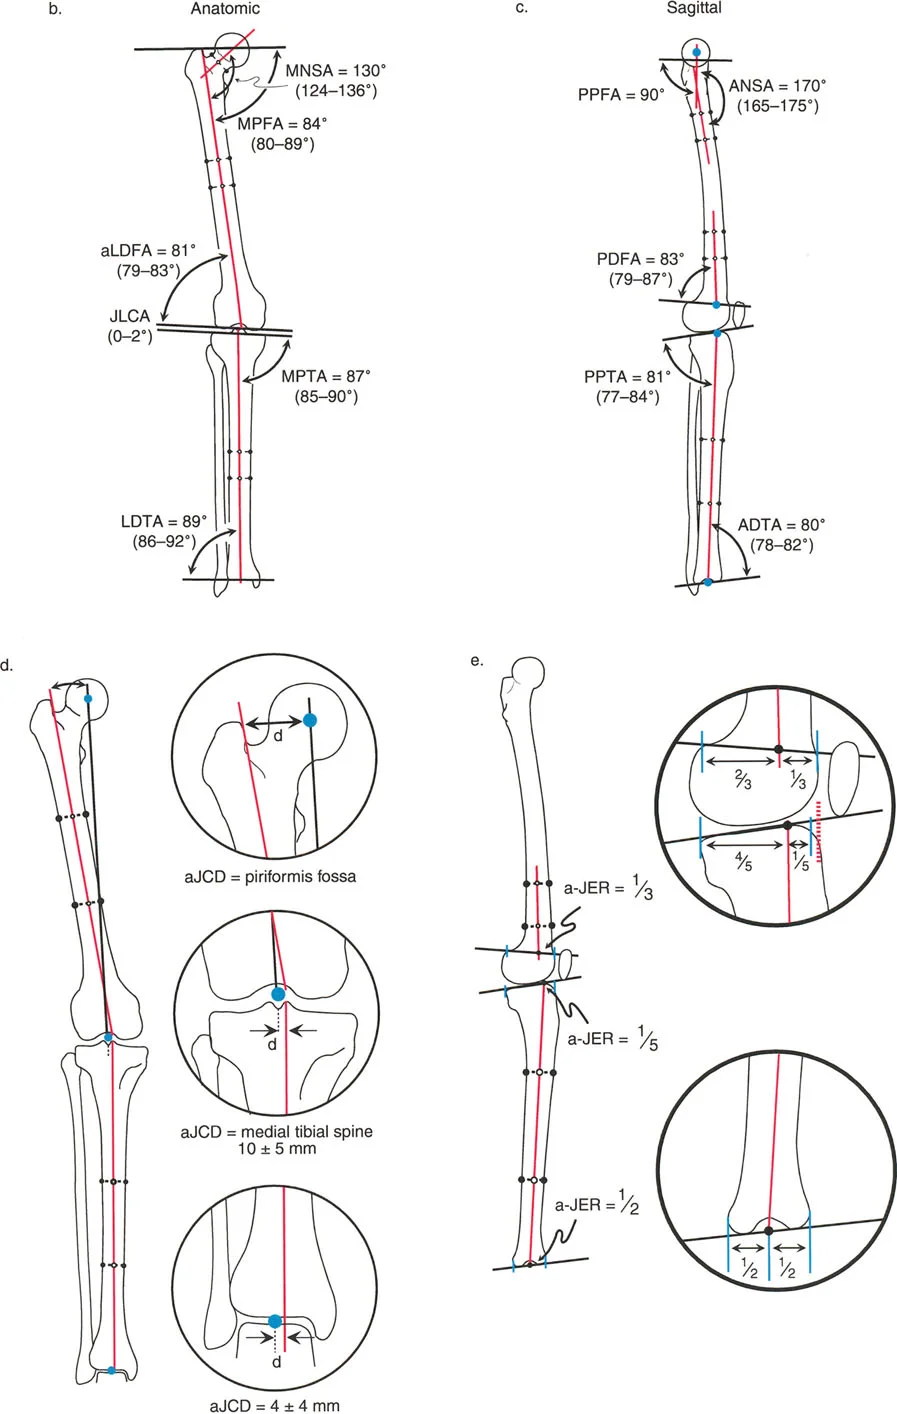

The nomenclature follows a strict formula: [Axis] + [Medial/Lateral] + [Proximal/Distal] + [Bone] + Angle.

- Axis: 'm' for mechanical, 'a' for anatomic.

- Side: 'M' for medial, 'L' for lateral, 'A' for anterior, 'P' for posterior.

- Location: 'P' for proximal, 'D' for distal.

- Bone: 'F' for femur, 'T' for tibia.

- Angle: Always ends with 'A' for Angle.

For example, mLDFA stands for the mechanical Lateral Distal Femoral Angle.

Frontal Plane Femoral Angles

- mLDFA (mechanical Lateral Distal Femoral Angle): The angle between the mechanical axis of the femur and the distal femoral joint line on the lateral side.

- Normal Value: 87° (Range: 85° - 90°)

- aLDFA (anatomic Lateral Distal Femoral Angle): The angle between the anatomic axis of the femur and the distal femoral joint line on the lateral side.

- Normal Value: 81° (Range: 79° - 83°)

- mLPFA (mechanical Lateral Proximal Femoral Angle): The angle between the mechanical axis of the femur and the proximal femoral joint line.

- Normal Value: 90° (Range: 85° - 95°)

Frontal Plane Tibial Angles

Because the mechanical and anatomic axes of the tibia are parallel, we generally refer only to the mechanical angles, which apply to both axes.

- MPTA (Medial Proximal Tibial Angle): The angle between the mechanical/anatomic axis of the tibia and the proximal tibial joint line on the medial side.

- Normal Value: 87° (Range: 85° - 90°)

- LDTA (Lateral Distal Tibial Angle): The angle between the mechanical/anatomic axis of the tibia and the distal tibial joint line on the lateral side.

- Normal Value: 89° (Range: 86° - 92°)

Joint Line Congruency Angle JLCA

The Joint Line Congruency Angle (JLCA) is measured between the joint line of the distal femur and the joint line of the proximal tibia. It evaluates the soft tissue envelope (ligamentous laxity) and cartilage wear of the knee.

* Normal Value: 0° to 2° (joint lines are nearly parallel).

* Clinical Significance: A JLCA greater than 2° indicates intra-articular deformity, such as collateral ligament laxity or asymmetric cartilage loss. If a patient has a varus deformity with a large JLCA, correcting only the bony deformity without addressing the ligamentous laxity will result in under-correction.

Sagittal Plane Angles

Sagittal plane analysis is equally critical, particularly for preventing recurvatum or procurvatum deformities that alter gait kinematics.

- aPDFA (anatomic Posterior Distal Femoral Angle): 83° (Range: 79° - 87°)

- PPTA (Posterior Proximal Tibial Angle): 81° (Range: 77° - 84°). This represents the natural posterior slope of the tibial plateau.

- ADTA (Anterior Distal Tibial Angle): 80° (Range: 78° - 82°).